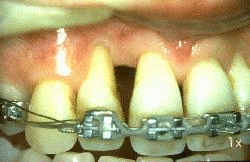

El procedimiento de Widman modificado fue realizado y la imagen muestra la apariencia clínica  7 días después del postoperatorio. El paciente se ha enjuagado dos veces por día con  chlorhexidine durante 7 días.

La imagen muestra 6 meses después del tratamiento. El paciente presenta una excelente higiene oral y al sondaje del surco gingival no presenta sangrado y evidencia una profundidad de 3 mm como máximo.